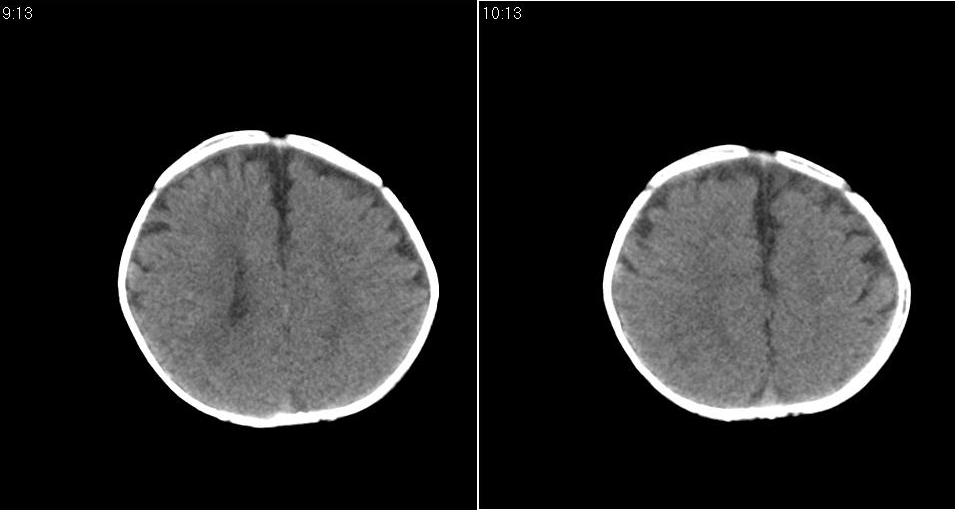

标题: PED1744:颅脑CT平扫

男 3个月,头大,颈软,头向后仰。

外部性脑积水

考虑外部性脑积水。

脑外间隙增宽,未见明显异常。

脑外间隙增宽,余未见明显异常。

脑外间隙增宽,现在好像有人说是一种发育性的交通性脑积水

蛛网膜增宽,外部性脑积水?

外部性脑积水(也就是诸位说的脑外间隙增宽);脑实质内未见异常密度灶,脑室系统无扩张,建议随访,毕竟临床症状听着怪吓人的。